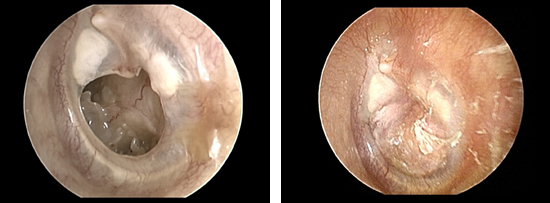

当科では、慢性中耳炎などで鼓膜に穴が開き(鼓膜穿孔)、聞こえや耳だれに悩んでいる方へ鼓膜形成術、また真珠腫性中耳炎などには鼓室形成術と、患者様に応じて最適な治療法をご提案し実施しております。

鼓膜形成術は「皮下結合組織を用いた接着法による鼓膜形成術」をメインに行っており、短期入院で手術が可能になる例が多く、場合によっては局所麻酔での「日帰り手術」も可能です。鼓室形成術においても入院期間ができるだけ短く、外来受診のときに、耳の処置がほとんど不要になるような手術方法を行っています。

鼓膜穿孔(左図)と鼓膜形成術後(右図)の内視鏡写真